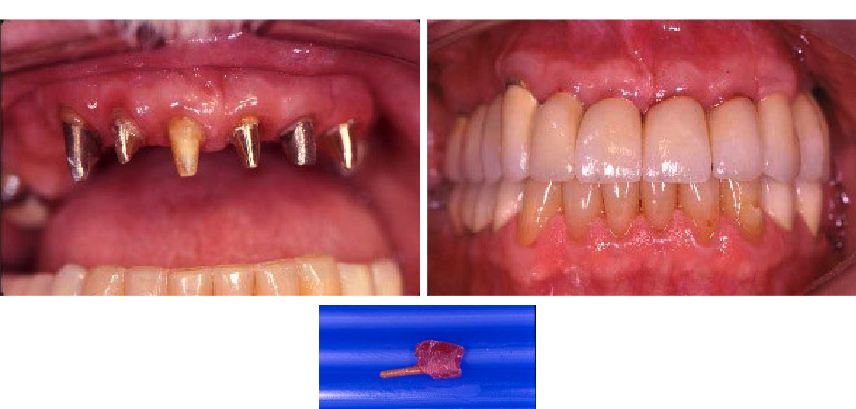

post/core (foundation restoration)

Incidence of complication for single restoration:

All ceramic crown %

Post/Core %

Conventional single crowns %

All ceramic crown 8%

Post/Core 10%

Conventional single crowns 11%

what are the most common complications for post/core?

Post Loosening 5%

Root Fracture 3%

Caries 2 %